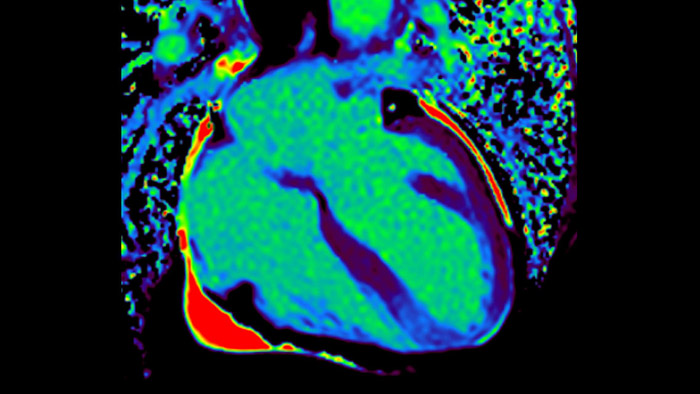

IntelliSpace Portal MR CaaS5,6 Strain7 supporta nella diagnosi e nel monitoraggio dei pazienti fornendo parametri globali di strain, quali strain longitudinale globale (GLS), strain circonferenziale globale (GCS) e strain radiale globale (GRS), utilizzando immagini RM in asse corto e lungo e descrivendo inoltre la deformazione del miocardio, come il suo accorciamento, ispessimento e allungamento durante il ciclo cardiaco.

La diagnostica tradizionale non offre la visibilità necessaria per vedere gli effetti di un trattamento cardiaco o individuare disfunzioni prima che si verifichino i sintomi. Combinando la sequenza di acquisizione MRI Fast-SENC di Philips con lo strumento di analisi MyoStrain di Myocardial Solutions, i lievi cambiamenti precoci nella funzione cardiaca possono essere misurati direttamente.

La diagnostica odierna spesso non è in grado di rilevare le disfunzioni cardiache fino a quando non si manifestano sintomi. MyoStrain valuta la deformazione del miocardio in 48 segmenti cardiaci e fornisce ai medici uno strumento diagnostico utile per identificare con anticipo la disfunzione funzionale prima che il cuore nel suo complesso sia compromesso.